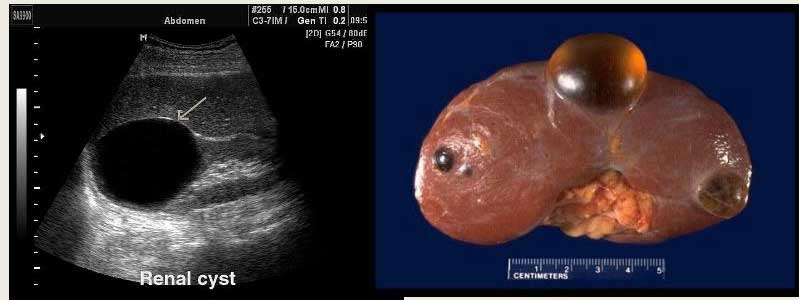

УЗИ почек. Обнаруживает округлое образование, которое локализуется в паренхиме органа или экстраренально.